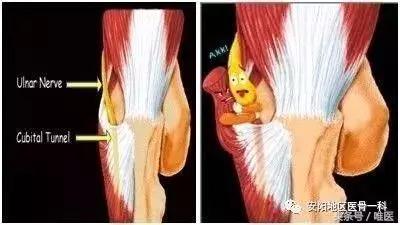

尺神經起自臂叢神經內側束(C8、T1神經根),在肘部區域,尺神經可受Struthers弓形組織、內側肌間隔、肱三頭肌內側頭、Osborne韌帶、尺側腕屈肌筋膜和深部的尺側腕屈肌腱膜等組織的卡壓。

“哎呦,我去,太專業了!”其實簡單地說,就是尺神經在肘關節處的通道(肘管)變窄了,卡住了,有些“反動勢力”對它進行了壓迫,從而使尺神經不能正常工作並受到損傷。

最常見的原因是肘部長期過度使用引起慢性損傷,構成肘管的各結構均可發生慢性損傷性炎症,使肘管管腔狹窄,尺神經在肘管內受壓;

其次是肘部急性損傷,肱骨遠端骨折、肘關節脫位等可引起尺神經急性或繼發受壓;

還有先天或後天性肘外翻、或肘管內發生腫瘤,尺神經被壓而產生一系列症狀。